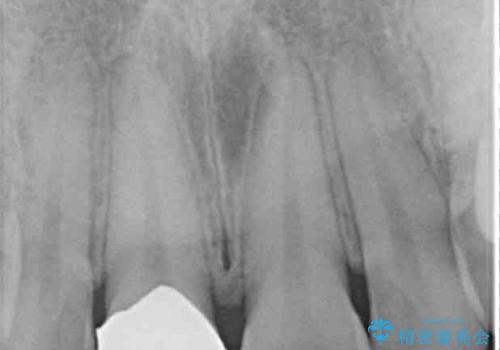

- 結婚式を前に、保険診療での前歯のクラウンが気になるとのことで来院された患者様です。

色合いだけでなく、歯肉の縁が黒くなっていることが分かります。

速やかに仮歯に交換し、オールセラミッククラウンにて補綴することとしました。

神経組織が健全な状態で残っている歯であったため、1ヶ月かからずに治療を終えることができました。